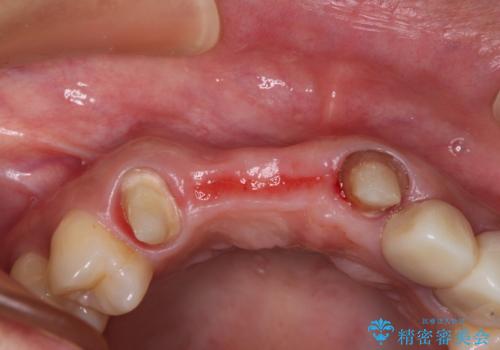

- 前歯を2本抜歯した後に装着した仮歯が長く見えるのが気になるとのことで来院された患者様です。

抜歯後には歯を支えていた骨が失われるため、歯肉が痩せてしまい、結果としてブリッジのダミーの歯を長くする必要があります。

前医では、歯肉の位置に相当する部分を、歯肉に近い色とすることで歯の長さが揃っているようにカムフラージュする治療が提案され、仮歯もそのようになっていました。

歯肉が痩せてしまっている状態を改善するため、口蓋から歯肉の結合組織を採取し、移植することで厚みを増大させることとし、その後オールセラミックブリッジにて補綴治療を行うこととしました。